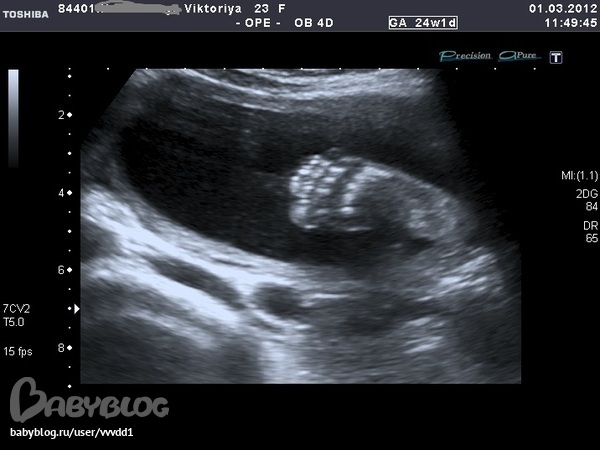

Результаты: УЗИ, КТГ, доплера, скринингаОчень понравилось,столько эмоций))))Пока мы ехали в больницу я слопала сникерс и уже в пути я начала ощущать пиночки.На узи нам подтвердили,что девочка.Малышка наша такая скромница, ручками глазки закрывала,пальчик сосет, а потом как дала боксом заниматься.Записали на диск видео, дали кучу фоток.Папа наш сидел,все налюбоваться не мог, говорит что она так на меня похожа.Весит наша принцесса 650 г.Врач очень хороший,много рассказывал,плацента поднялась,никаких аномалий развития не выявлено,Боже,как я попереживала за эту плаценту,как я рада,что все обошлось,а вот собственно и фотки нашего счастья